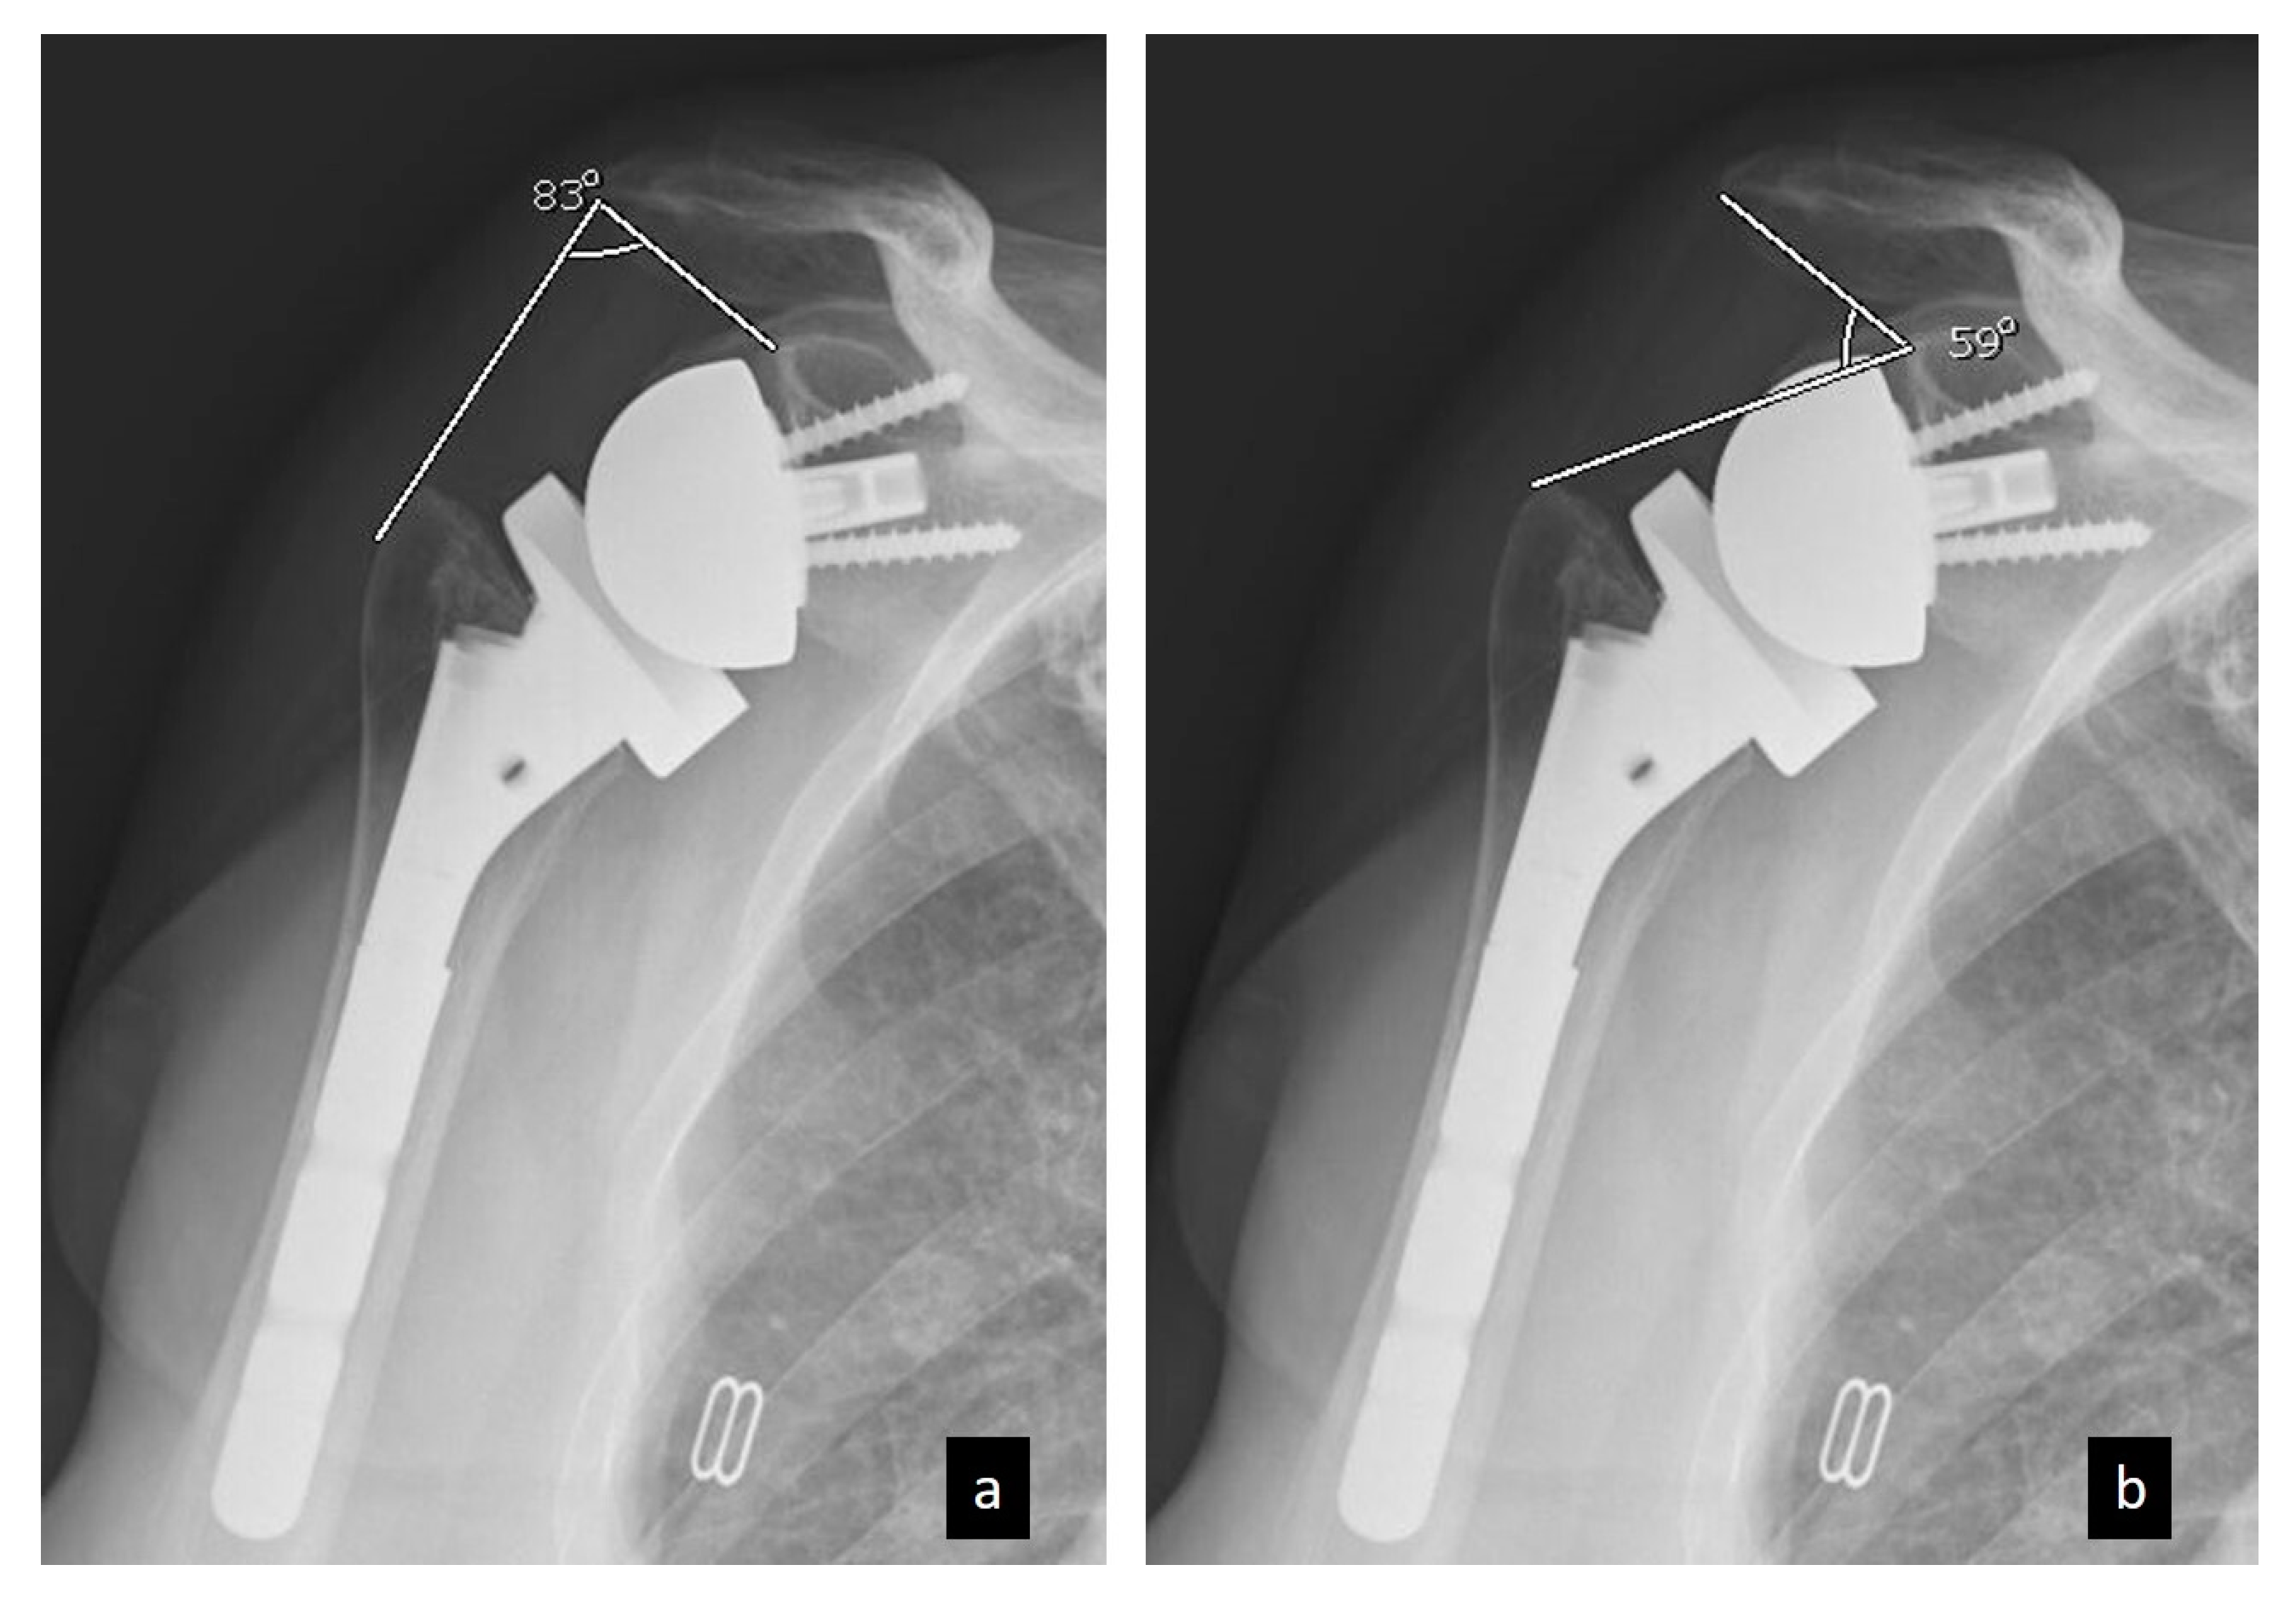

On postoperative radiograph images, LSA and DSA were measured following the method described by Boutsiadis et al. [11]. LSA was defined as the angle formed between the line connecting the superior glenoid tubercle to the most lateral border of the acromion and the line extending from the most lateral edge of the acromion to the most lateral edge of the greater tuberosity (Figure 1). DSA was defined as the angle formed between the line extending from the most lateral edge of the acromion to the superior glenoid tubercle and the line extending from the superior glenoid tubercle to the most superior edge of the greater tuberosity (Figure 1).

Figure 1. Radiological measurements of (a) lateralization shoulder angle (LSA) and (b) distalization shoulder angle (DSA) on a true anteroposterior shoulder radiograph.